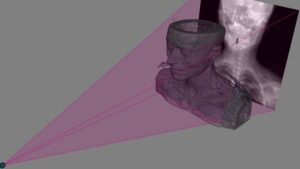

El Hospital General Universitari de Castellón (HGUCS) ha colaborado en la tesis doctoral de la Universitat Jaume I 'Hallazgos radiológicos de la tuberculosis pulmonar y su correlación con la presencia de cultivo positivo para Mycobacterium tuberculosis' que ha obtenido una calificación de Sobresaliente Cum Laude. Su autor ha sido Antonio Navarro Ballester, que fue médico interno residente (MIR) de Radióloga del centro sanitario.

Asimismo, el trabajo de Navarro ha sido dirigido por los facultativos, también doctores, Santiago F. Marco Doménech y Luis Lizán Tudela. Además, ha contado con la intensa colaboración del Servicio de Microbiología y Parasitología y del de Radiología Diagnostica y Terapéutica.

Por su parte, Antonio Navarro ha logrado elaborar un sistema de puntuación predictiva, a través de una regresión logística multivariante, que permite establecer el diagnóstico de tuberculosis pulmonar utilizando datos clínicos, epidemiológicos, de radiografía simple de tórax y TAC torácico.

Por su parte, Antonio Navarro ha logrado elaborar un sistema de puntuación predictiva, a través de una regresión logística multivariante, que permite establecer el diagnóstico de tuberculosis pulmonar utilizando datos clínicos, epidemiológicos, de radiografía simple de tórax y TAC torácico.